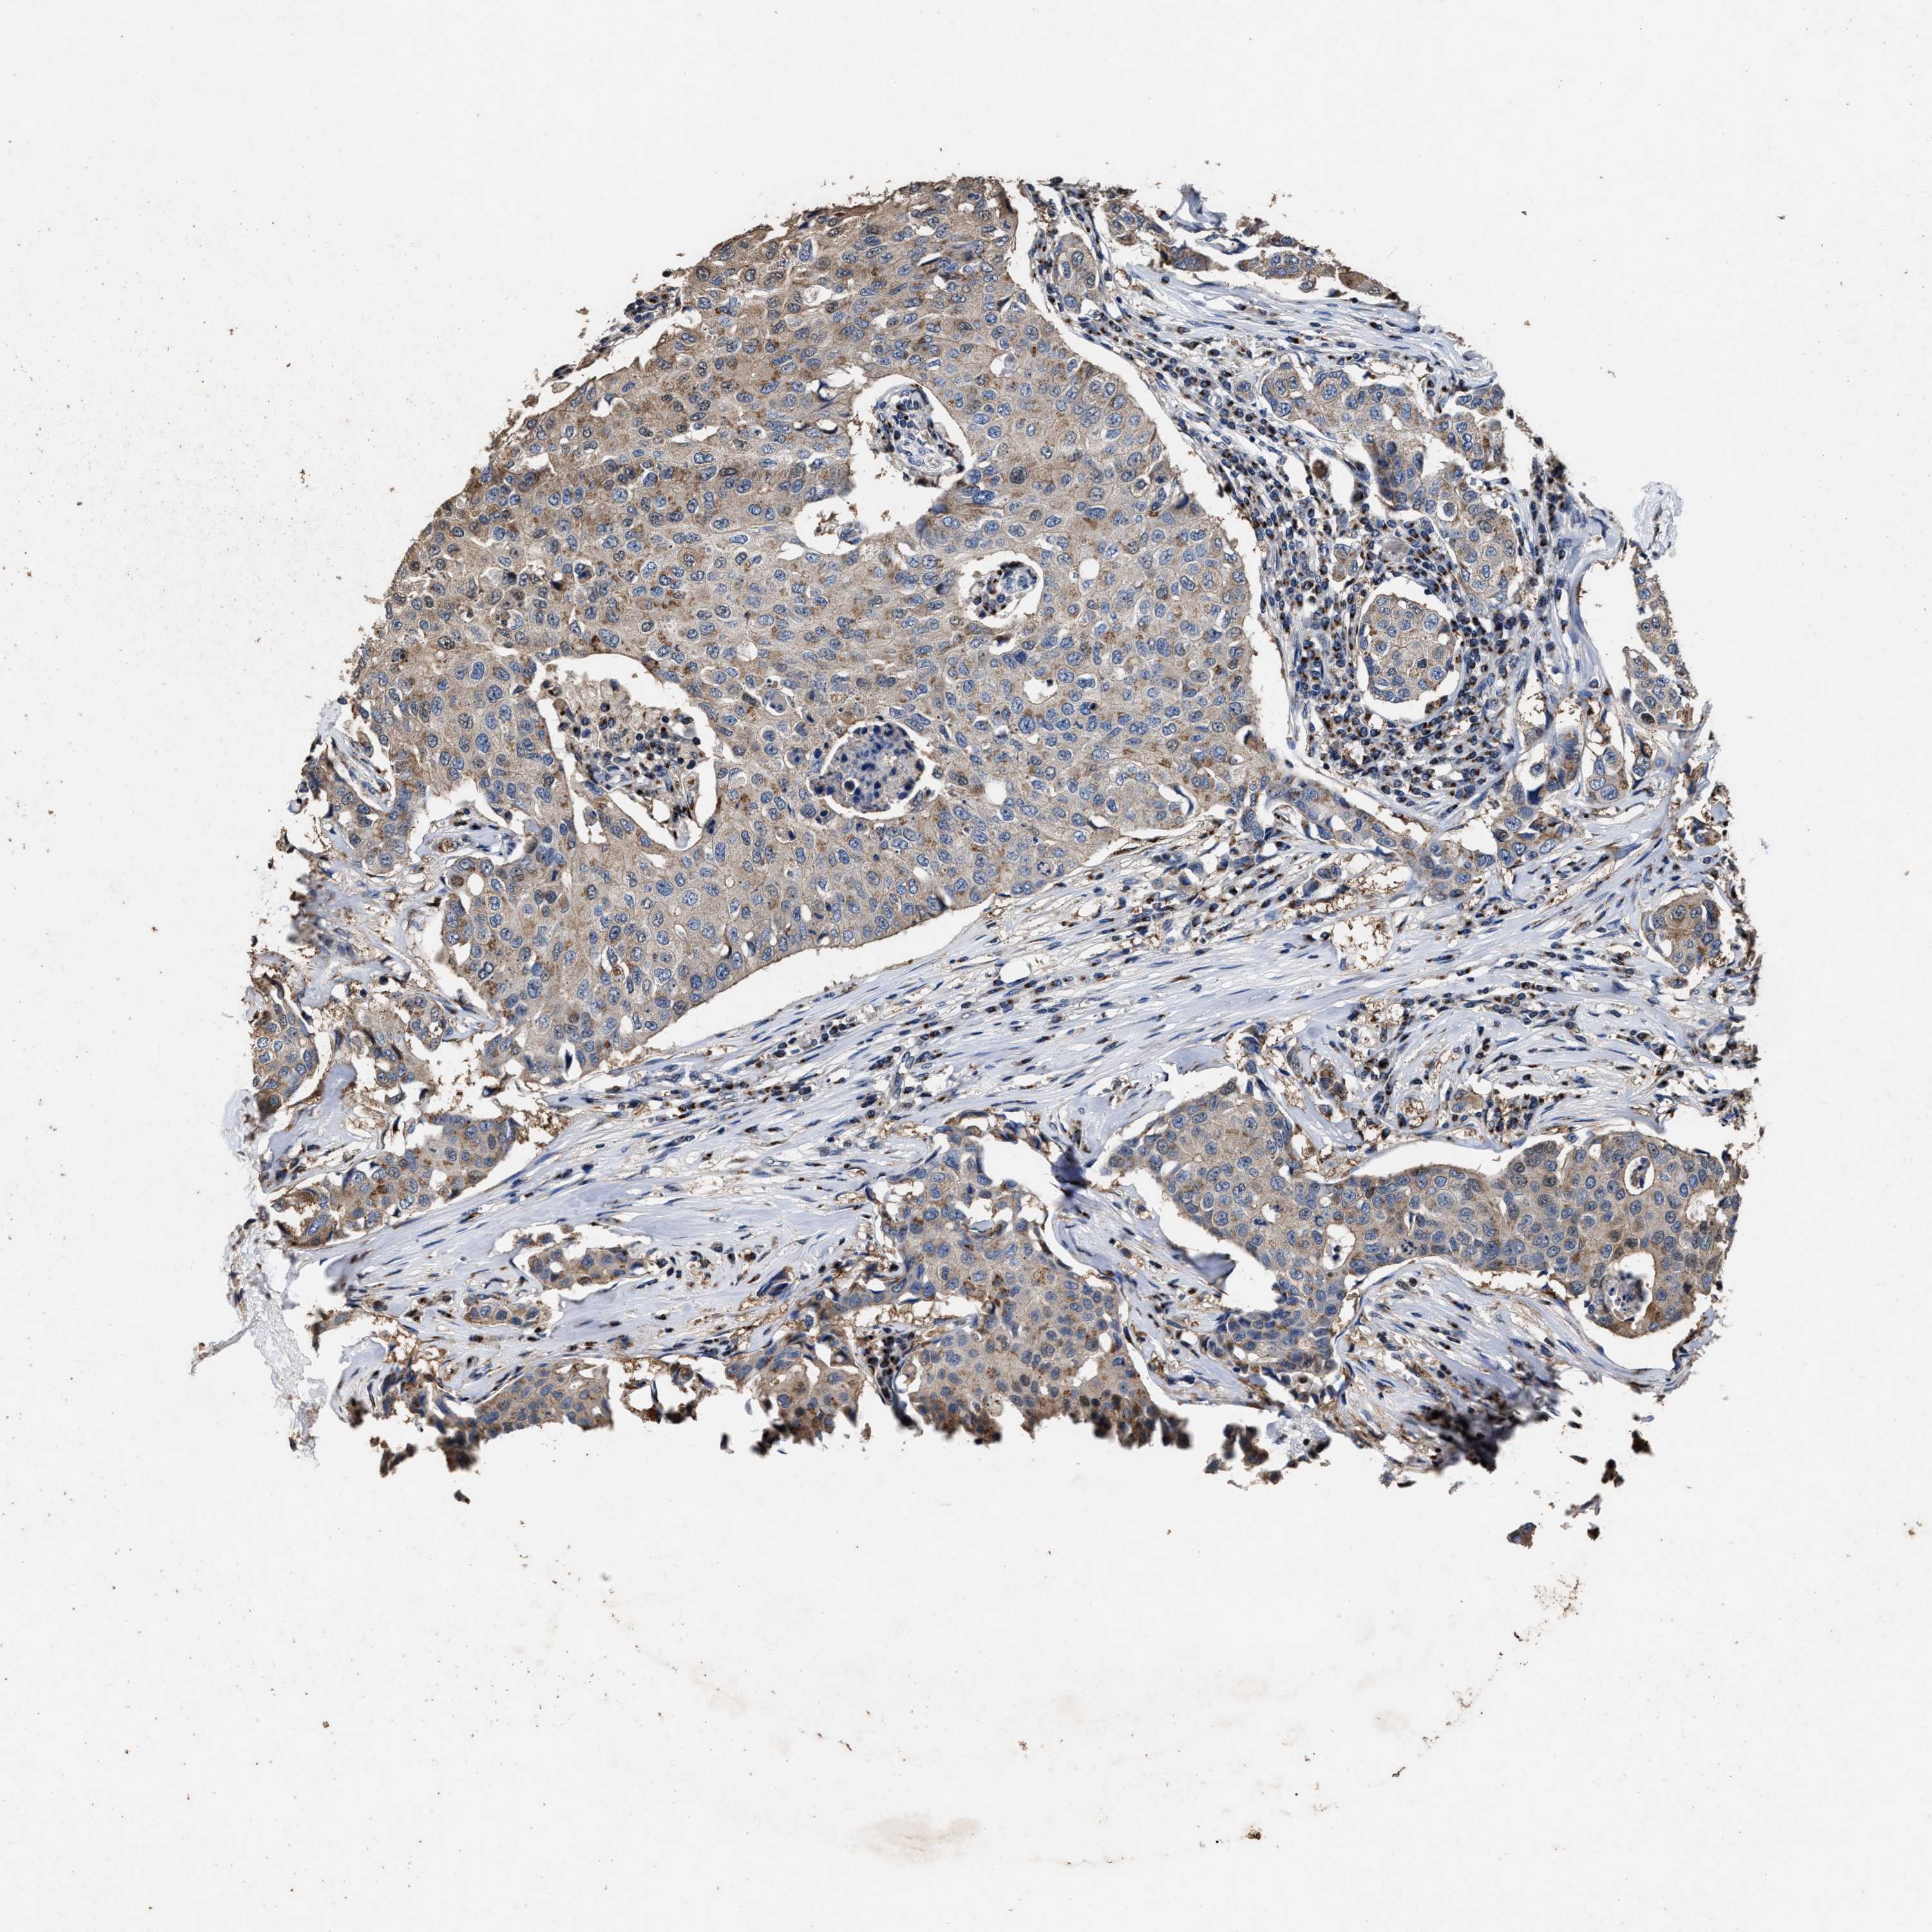

CANCER BREAST CANCER Show tissue menu

BRCA TCGA BRCA VALIDATION PROTEIN EXPRESSION

Breast cancer

Human cancer